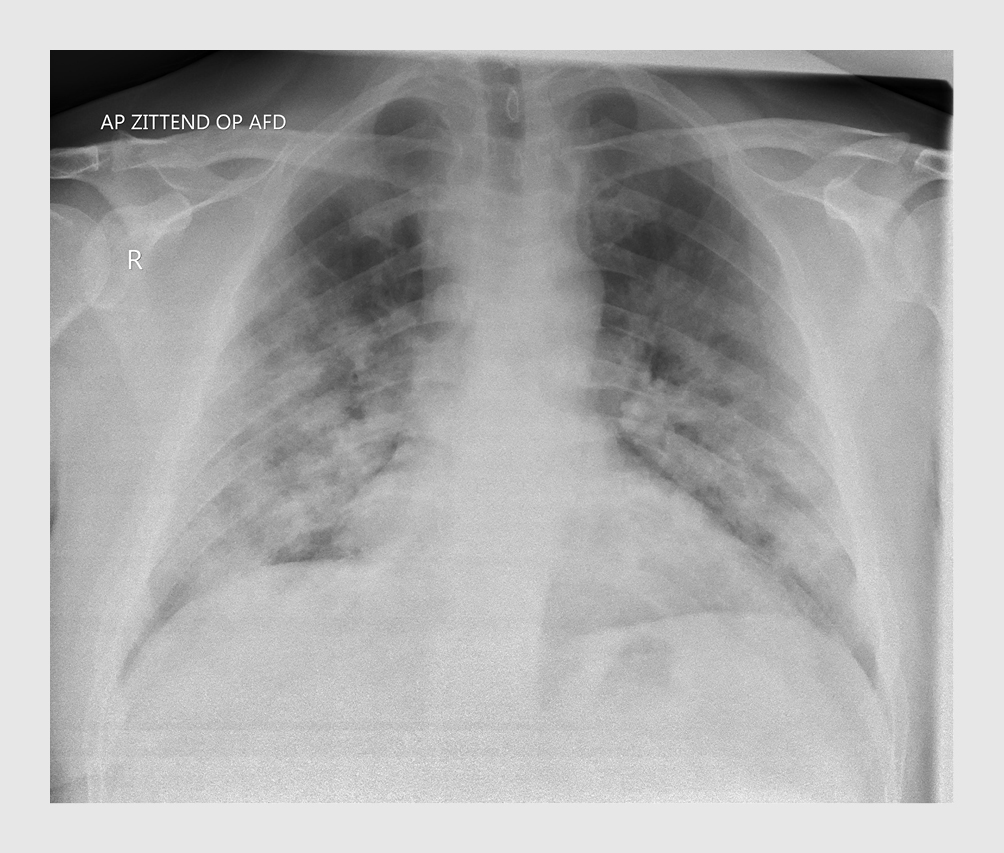

Consolidaties werden gezien op 3 thoraxfoto’s (10,7%), toegenomen interstitiële tekening op 4 (14,2%) en een combinatie van toegenomen interstitiële tekening en consolidatie op 13 foto’s (46,4%). Bij de meeste patiënten waren dit perifeer gelegen, diffuus verspreide afwijkingen (figuur 1).

Figuur 1

Afwijkingen op longfoto bij COVID-19

Figuur 1 | Afwijkingen op longfoto bij COVID-19

Röntgenfoto van 1 van de 29 eerste patiënten met COVID-19 uit een ziekenhuis in Noord-Brabant met perifeer gelegen, diffuus verspreide afwijkingen. Op 46,6% van de foto’s was een combinatie van beiderzijds toegenomen interstitiële tekening en consolidaties te zien, zoals op dit voorbeeld.